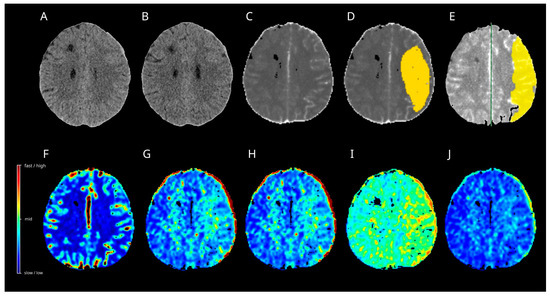

3.10. Case 1